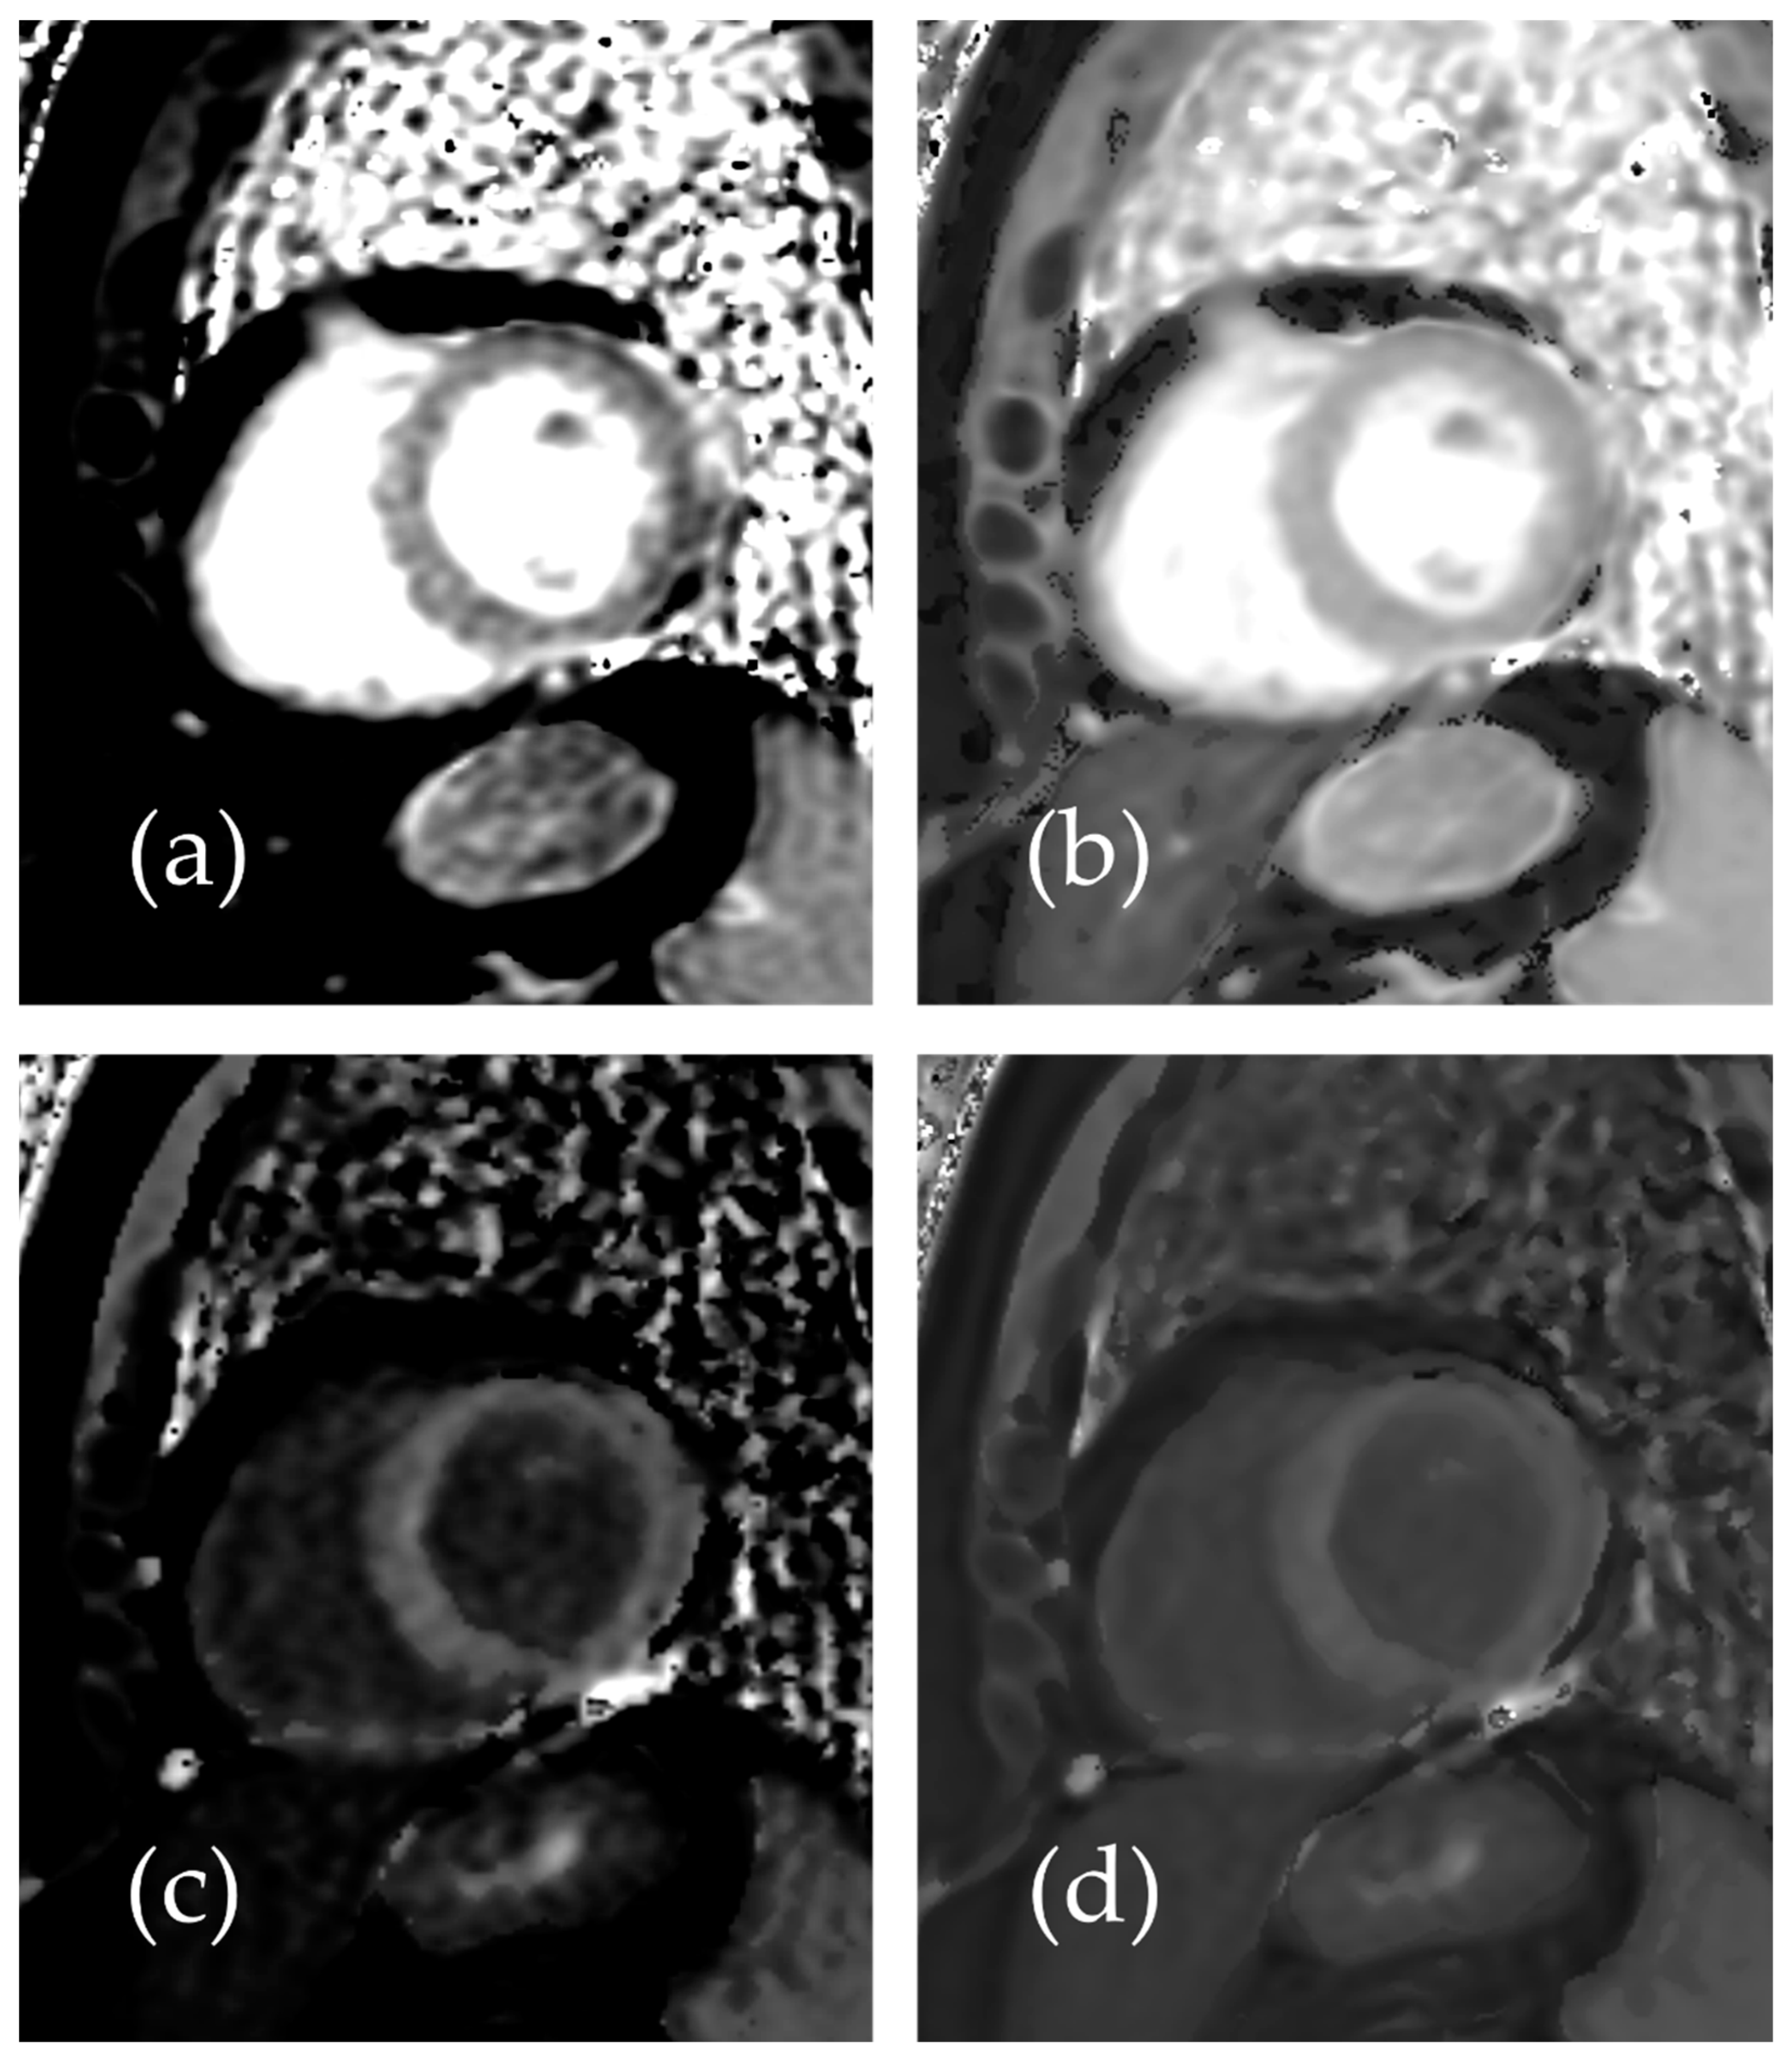

2. Materials and Methods

3. Results

3.1. Patient Study

3.2. Phantom Study